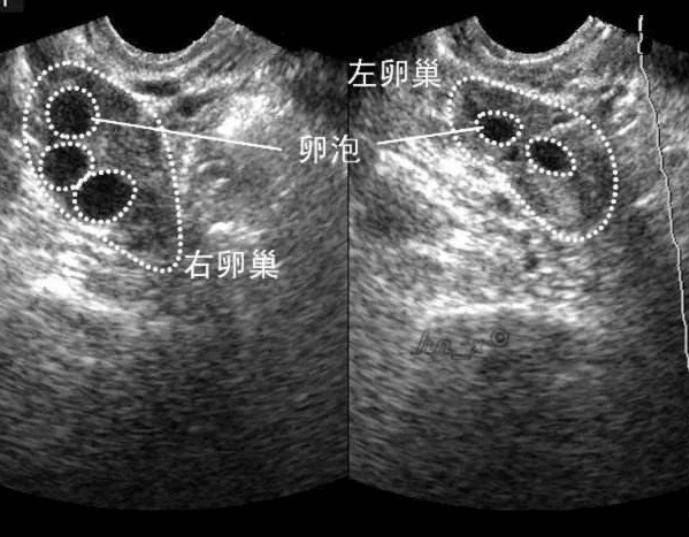

卵泡發育不好漳州市醫院的試管之路,掌握這個方法離寶寶更近一步

測出懷孕這麼久才寫下自我的感想,主要想給那些黃體不足,卵泡不發育的姐妹一些信心。我是去年8月開始備孕的,之前為了要孩子,養胖了10斤。8,9月相信同房的次數少,精子質量才高的說法,我只在排卵期A一次,心想懷孕是件很容易的事情。誰知8、9月沒懷上。然後在10月排卵期隔天A一次,但老公的精力似乎不行。第三次就不行了。當月還是沒懷孕。11月排卵後去漳州市醫院B超檢測,醫生說貌似已經排過卵。不知為何從我開...